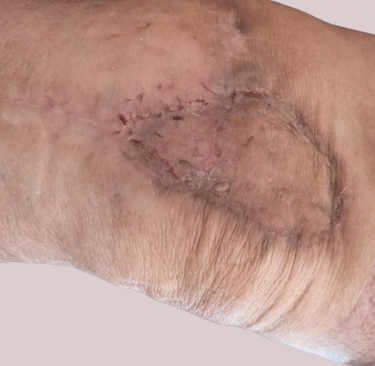

Grefa de piele este o porțiune de țesut cutanat recoltată de la pacient (autogrefă) sau, mai rar, de la un donator (homogrefa), care este apoi transplantată pe o zonă unde pielea lipseste sau este profund afectată. Scopul acestei intervenții este de a acoperi plăgi extinse, cronice sau acute, și de a favoriza vindecarea funcțională și estetică.

Complicații posibile

Necroza parțială sau totală a grefei (în lipsa prinderii),

Infecția grefei sau a zonei donatoare,

Durere sau disconfort persistent,

Diferențe de culoare sau textură între grefă și pielea din jur,

Cicatrici hipertrofice sau inestetice (atât la locul donator, cât și la cel primitor),

Necesitatea unei reintervenții.